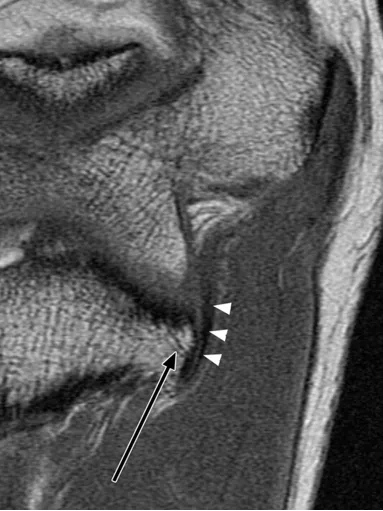

后方滑膜皱襞,是肘关节内滑膜折叠形成的结构,若受到反复刺激可能诱发炎症反应。

(a)26 岁男性受试者的横轴位质子密度加权脂肪抑制磁共振成像,以及(b)对应的示意图,均显示出后方滑膜皱襞(箭头所示)。图中 AM 代表肘肌。